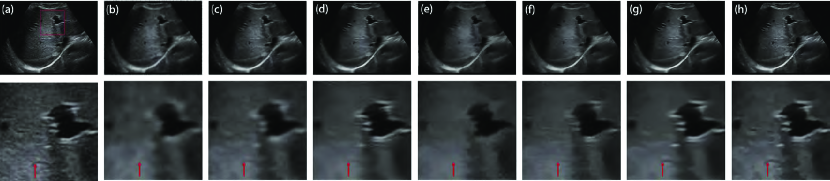

The real ultrasound image experiment has no ground truth image and gold standard to find the optimal parameters in terms of quantifiable performance criteria. Thus, we adjust the parameters of the PFDTV method to obtain the best visual effect. The visual performance of our method is closely associated with three parameters: , and . According to the analysis in Section II-A, we set the scale of the PAS measure as . is a positive constant that is related to the the noise level, and is the number of iterations.

The parameter is an important parameter that is related to the noise level estimation. Noise level estimation is a prerequisite for various detail-preserving image denoising methods [21] but has remained as an unsolved challenging problem in ultrasound image despeckling. According to (16), if is set to a large value, a large diffusion coefficient is obtained that will cause some details to be damaged after speckle reduction. However, if is set to a small value, a small diffusion coefficient is achieved that will increase computational costs in the despeckling process. To explore the impact of parameter , we set with different values. Fig. 4 depicts the despeckled results of different . It is observed that there is a significant level of noise in the despeckled result of . As indicated by the red arrow in Fig. 4(d), the meaningful detail is damaged after noise removal in the case of . Our method achieves not only satisfactory feature preservation but also desirable noise reduction in the case of . In real image experiments, we find that the best range of is from to . Here, we set as .